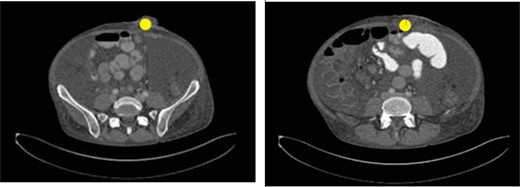

Seven weeks after colostomy creation, the patient presented as a core trauma activation due to a mechanical fall that resulted in colostomy disruption and evisceration of abdominal contents (Figs 2 and 3). The patient reported a fall down several stairs where he struck his abdomen. On presentation, he was neurologically intact and hemodynamically stable. He was found to have no additional traumatic injuries after workup was completed.

Image taken upon presentation to the emergency department with left lower quadrant ostomy evisceration marked (yellow circle). Oral contrast reaches the mid small bowel. Scattered small bowel loops are mildly prominent measuring up to 3.7 cm in diameter. The colon appears thick-walled particularly along the ascending aspect. There is no pneumatosis. There is no discrete hernia. Findings are consistent with small bowel obstruction.